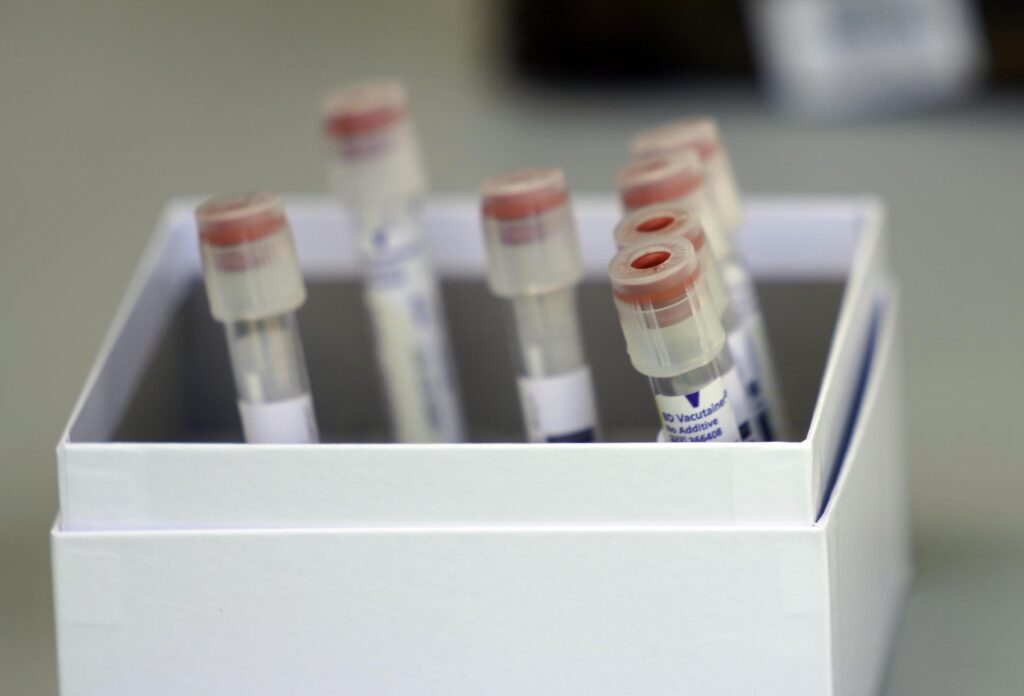

Diagnosticul de cancer de prostată se poate pune în stadii incipiente, cu ajutorul unor teste de screening și al metodelor moderne de diagnostic. Care sunt acestea aflăm de la Dr. Roxana Macarie-Priceputu, medic specialist oncologie.

Cancerul pulmonar rămâne principala cauză de mortalitate oncologică în România și a doua ca frecvență, cu circa 12.000 de cazuri noi diagnosticate anual, cele mai multe fiind depistate în fază finală.